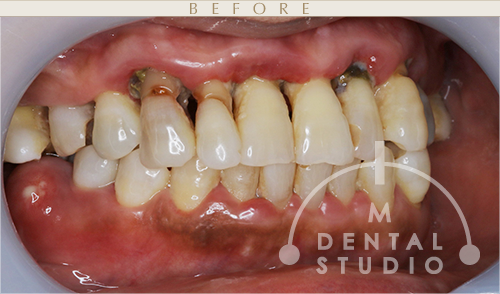

正面写真(術前)

この上の「前歯」は、ピアノの鍵盤のようにグラグラであり、更に虫歯が酷くボロボロでした。ご自身でも歯磨きをしたくても、もう~どうにも出来ない!って感じです。

しかし、「上下の前歯」は、抜歯をすることなく助けていきます。

左側写真(術前)

術前は歯ぐきの色は赤く、ポコポコと歯ぐきは腫れて、さらに黒ずむくらいかなり痛々しいです。